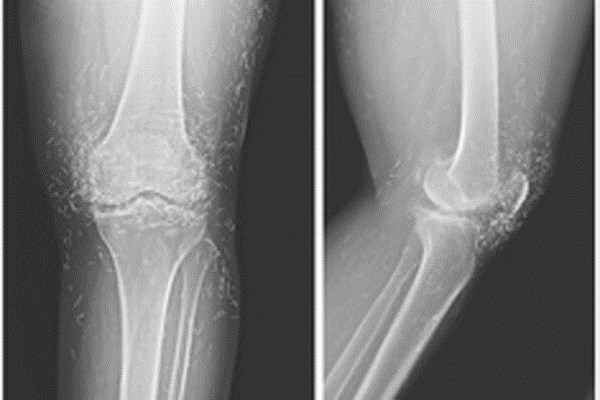

| Khi các bác sĩ kiểm tra phim chụp X quang hai đầu gối của một cụ bà 65 tuổi người Hàn Quốc do bị đau khớp nghiêm trọng, họ phát hiện một "mỏ vàng” là hàng trăm chiếc kim châm cứu tí hon bằng vàng, bị bỏ lại trong mô của bà. Trong quá trình châm cứu cho cụ, các thầy thuốc y học cổ truyền đã cố tình để lại những chiếc kim làm bằng vàng găm trong mô của bà để tiếp tục tạo ra sự kích thích. Tuy nhiên, bác sỹ cho biết, các vật thể lạ bị bỏ lại bên trong cơ thể có thể dẫn tới tình trạng viêm, áp xe và nhiễm trùng. Chúng cũng có thể gây khó khăn cho bác sĩ đọc phim X quang. |